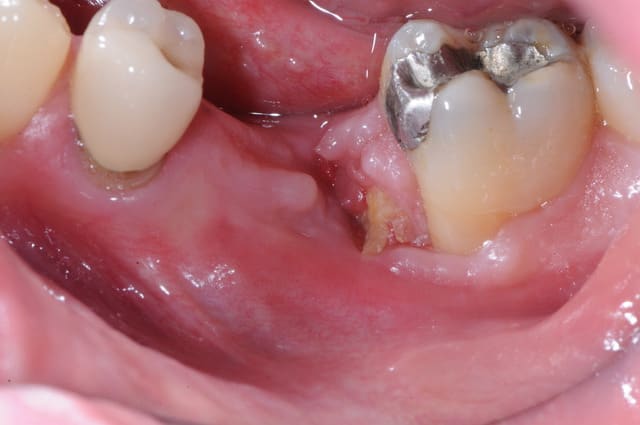

patient qui consulte lundi dernier pour avis implantaire pour 46

je regarde et je vois un petit morceau osseux bien vilain qui dépasse.

l'extraction a eu lieu il y a 4 mois par un confrère qui bosse bien et donc je ne remet pas en cause ses compétences.

l'extraction s'est pourtant bien déroulée et d'après le patient, les suites aussi. là j'en doute un peu plus mais bon...

je lui ai programmé rapidement une intervention pour ce matin afin de cureter.

il a simplement fallu tirer un peu sur le séquestre